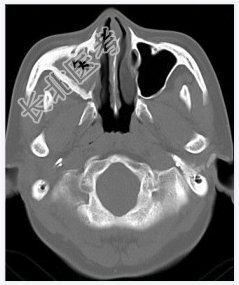

- [材料题] 女性,50岁。鼻塞2年余,有异物感,有血性分泌物,伴面颊疼痛。行CT检查。

- 简答题1、患者的诊断及依据是什么?

- 简答题2、需要与哪些疾病鉴别?